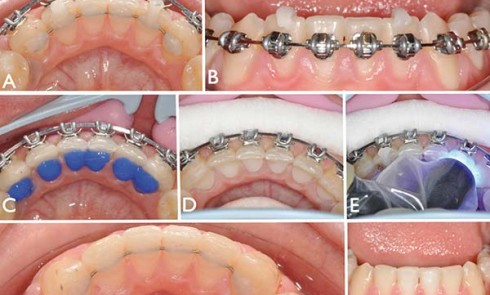

Article réservé à nos abonnés Geste clinique

Après avoir observé des mouvements dentaires anormaux sur des dents supportant un fil collé depuis une période allant de quelques...